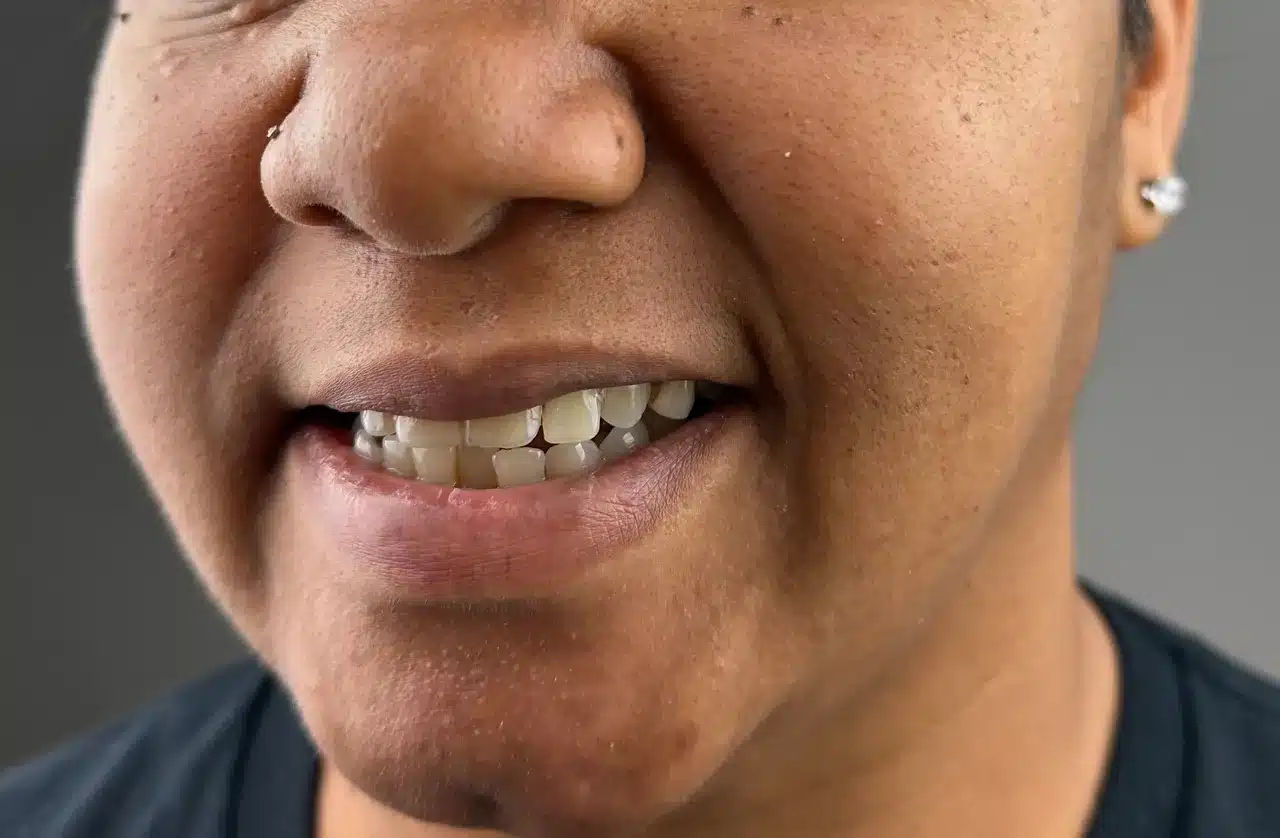

After